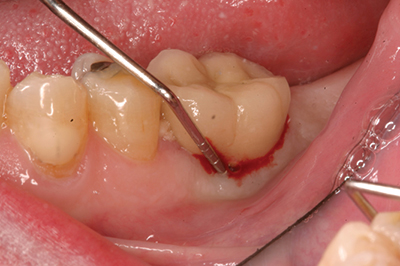

Peri-implantitis has been defined as an inflammatory process that affects the tissues around an osseointegrated implant in function and, like periodontitis, results in loss of supporting bone6 (Figs. 3 and 3a). The prevalence of peri-implantitis has been shown in some studies to range from 11% to as high as 47% of implant sites analyzed.(16) Most literature reviews agree that once bone loss has occurred around an implant, nonsurgical therapy is not as effective as surgical treatment.(17) Surgical intervention by the dentist or specialist includes raising a full thickness flap around the affected dental implant in order to completely expose the dental implant surface (Fig. 4). Mechanical debridement with hand and high-speed instrumentation as well as irrigation with various medicaments is advocated in order to detoxify the implant surface and alleviate bacterial contamination. After decontamination, the flap can be apically or coronally positioned. In addition, various regenerative technologies, including bone and soft-tissue grafts, growth factors, and barrier membranes have been used to rebuild lost tissue support around the dental implant (Figs. 5 and 5a). Different methods of guided bone regeneration around implants affected with peri-implantitis were demonstrated, and the results have been shown to be stable for a follow-up period of up to seven years.(18) That being said, no gold standard of peri-implant disease has been documented and "available evidence does not allow specific recommendations for the therapy of peri-implantitis."(19)